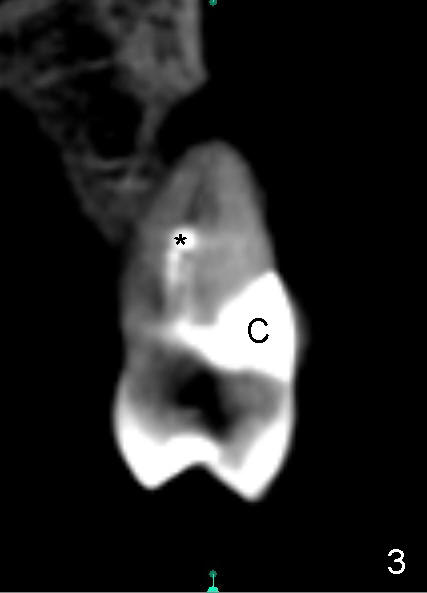

A 72-year-old lady has a deep cervical defect of the tooth #12 (Fig.1 ^) associated with buccal apical fistula (*) and periapical radiolucency (Fig.2 *). To prevent bleach leakage during root canal therapy (RCT), composite is used to repair the defect (Fig.3 (CT coronal section) C) prior to access. The buccal canal is not located probably due its own or iatrogenic (due to composite) obliteration. After thorough debridement of the lingual canal, Calcium Hydroxide paste is placed (*).